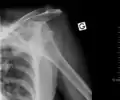

Inferior dislocation is the least likely, occurring in less than 1%. This condition is also called luxatio erecta because the arm appears to be permanently held upward or behind the head.[15] It is caused by a hyper abduction of the arm that forces the humeral head against the acromion.[16] Such injuries have a high complication rate as many vascular, neurological, tendon, and ligament injuries are likely to occur from this mechanism of injury.